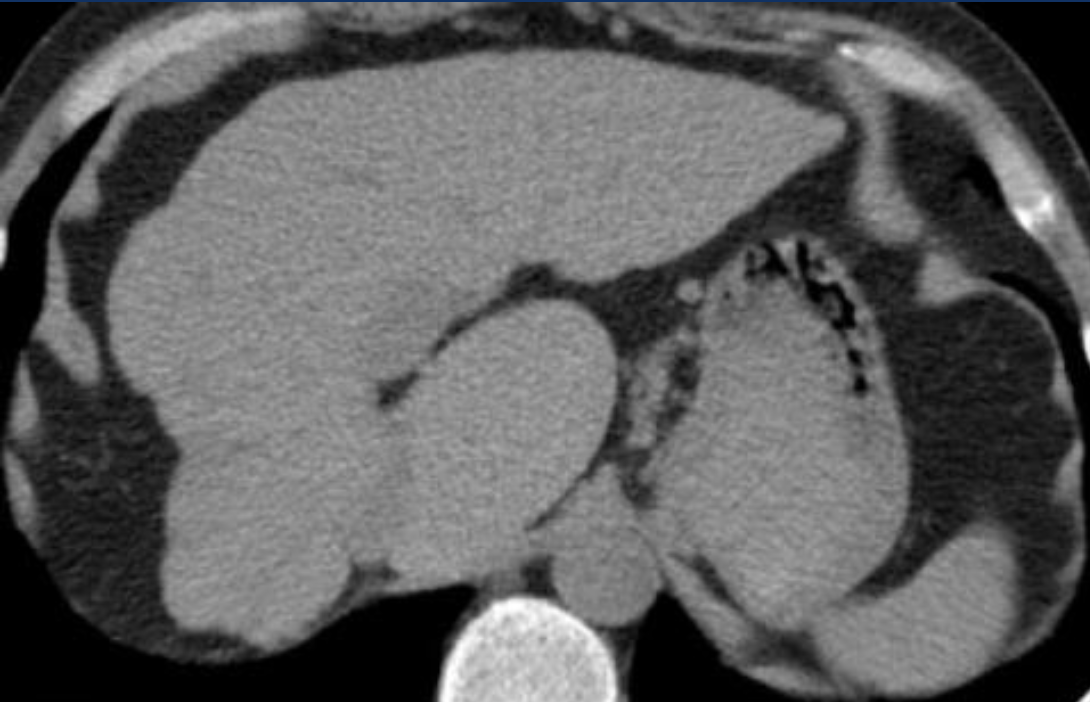

CT of the liver

Ix: NCCT normal app of liver relative to spleen; HUs.

Ix: liver should be slightly hyperattenuating relative to spleen; normal liver 10HU < spleen.

Normal liver attenuation